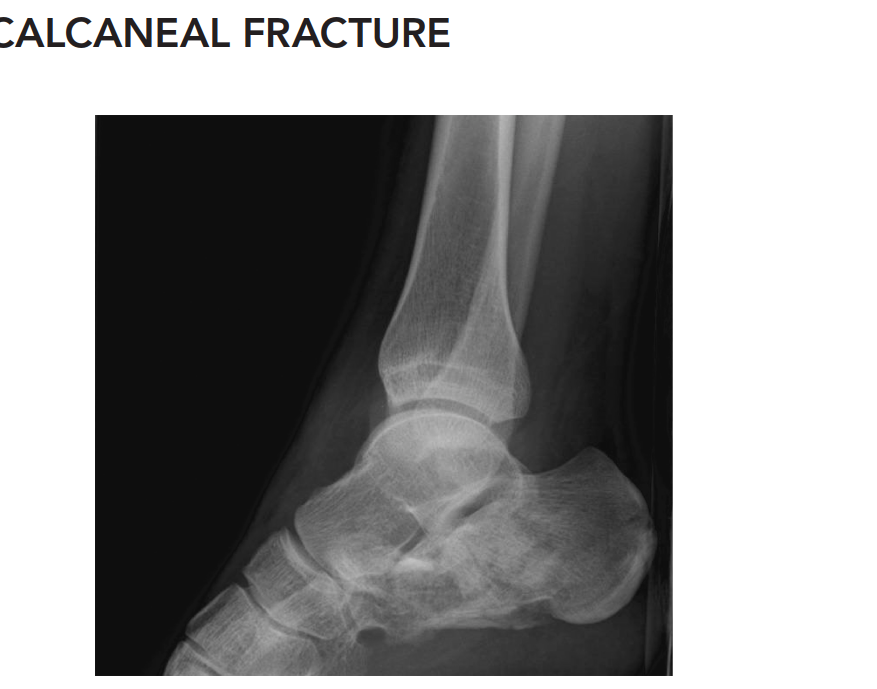

Lateral View:

Demonstrated a significant decrease in Bohler's angle (measured at 5 degrees, normal 20-40 degrees), indicative of substantial collapse of the posterior facet and loss of calcaneal height. Gissane's angle (Crucial angle) was increased to 140 degrees (normal 100-120 degrees), reflecting the disruption of the lateral process of the talus and the primary fracture line. There was clear evidence of a tongue-type fracture pattern with extension into the subtalar joint. Loss of calcaneal length and significant posterior facet depression were also evident.

Axial (Harris) View:

Revealed marked broadening of the calcaneus and a varus malalignment of the tuberosity. Significant comminution of the lateral wall was observed. Disruption of the sustentaculum tali was also suspected.

AP Ankle View:

Showed no evidence of ankle mortise injury, pilon fracture, or fibular fracture.